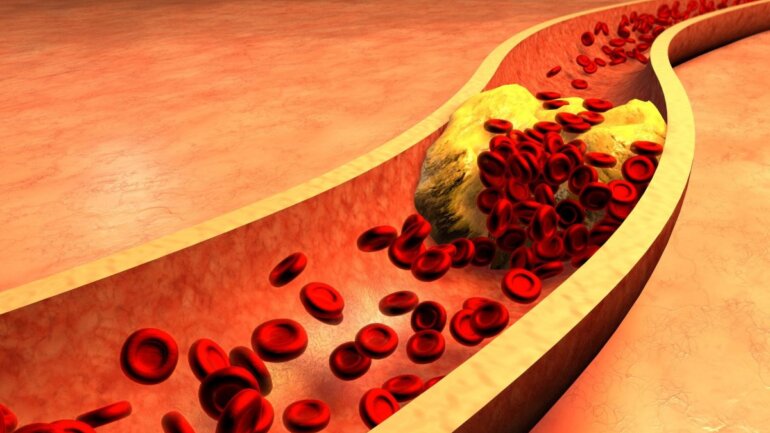

Τα PFAS σχετίζονται με αυξημένο κίνδυνο καρδιαγγειακών παθήσεων

Τα αποτελέσματα της τρέχουσας μελέτης υποδηλώνουν ότι ακόμη και οι σχετικά χαμηλές συγκεντρώσεις PFAS στο αίμα σχετίζονται με δυσμενή προφίλ λιπιδίων του αίματος.